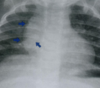

TBC postprimaria: cavidades y tractos fibrosos.

58